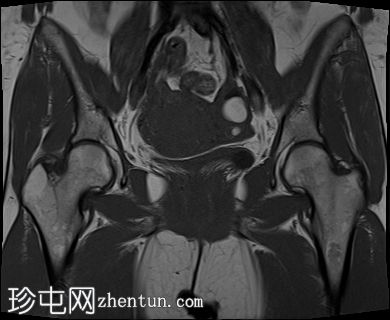

冠状位

T2加权像

3.jpg

增大的子宫腹股沟区(AVF)显示:

子宫前壁交界区局灶性增厚,边界不清。形成直径约3厘米的局灶性肿块样病变,轻度压迫膀胱。肿块边界模糊不清,可见多个细小出血灶,在T1加权像和T2加权像上均呈高信号,提示局灶性子宫腺肌症。

子宫体前壁可见另一处病灶,位于上述病灶尾侧,边界清晰(有包膜)。该病灶在T1和T2加权像上均呈低信号,内部未见异常信号灶,周围可见少量明显血管通道,提示为小型子宫肌瘤。

左侧卵巢可见数个小囊肿,在T1加权像上呈高信号,在T2加权像上呈低信号(T2阴影),T1脂肪抑制序列未见信号下降,提示其为血液降解产物。最大的囊肿轴位大小约为3.1×1.7 cm,轻度压迫卵巢实质。

右侧卵巢可见黄体囊肿。未见实性肿块。

边界模糊不清是局灶性子宫腺肌症(无包膜)的特征。此外,病灶内存在多个微小的内部出血灶(异位腺体),且邻近增厚模糊的交界区,这些都是局灶性子宫腺肌症的诊断标准。

在上述病灶尾侧可见另一处具有不同影像学特征的病灶,该病灶边界清晰(有包膜),且信号均匀(无微小的内部出血灶),提示可能合并子宫肌瘤。